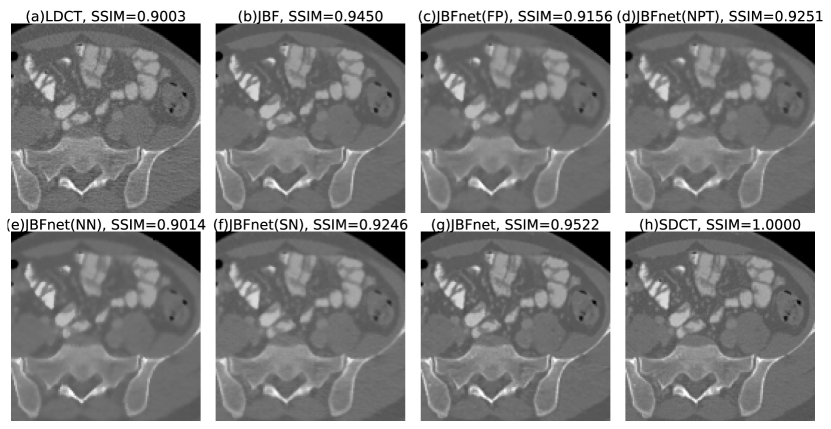

Refer to caption

Figure 4: We display a close-up example of (a) low dose CT, denoised by (b) JBF (c) JBFnet with frozen prior (FP), (d) JBFnet with no pre-training (NPT), (e) JBFnet with no NM (NN) added (f) JBFnet with single-weight NM (SN) added (g) JBFnet, and finally we display (e) the standard dose CT. SSIM scores are displayed in the captions. JBFnet achieves the best performance (SSIM = 0.9522). Images are displayed with a window of [-800, 1200].

3.3 Ablation Study

3.3.1 Training the Filtering Functions

Usually, the filter functions F𝐹F and G𝐺G of the bilateral filter are assumed to be Gaussian functions. We check if representing these functions with convolutions improves the denoising performance of our network. Training the filtering functions reduces our PSNR (w = 0.0, p = 0.005) but improves our SSIM (w = 0.0, p = 0.005) (Table 1 and Fig. 4).

3.3.2 Pre-training the Prior Estimator

In our current training setup, we exclusively train the prior estimator P𝑃P for 10 epochs, to ensure a good quality prior image. We check if avoiding this pre-training, or freezing the value of P𝑃P after training improves the performance of our network. Both freezing P𝑃P and not doing any pre-training reduce the PSNR and SSIM (w = 0.0, p = 0.005) (Table 1 and Fig. 4).

3.3.3 Pixelwise Mixing of the NM

Currently, we estimate the amount of the NM to be mixed back in by generating pixelwise coeffecients from a single 3 ×\times 3 convolution of the NM. We check if not adding in the NM, or adding in the NM with a fixed weight improves the denoising performance of the network. Not mixing in the NM reduces our PSNR and SSIM significantly (w = 0.0, p = 0.005). Mixing in the NM with a fixed weight reduces both PSNR and SSIM even futher (w = 0.0, p = 0.005) (Table 1 and Fig. 4).